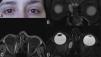

A 25-year-old woman with right subacute sinusitis complained about discomfort in her right eye. Clinical manifestations and computed tomography were suggestive of sub-periosteal orbital ethmoid wall abscess, for which the patient underwent urgent drainage. A solid tumor was found, with a positive biopsy for alveolar rhabdomyosarcoma. Complete remission and resolution of orbital symptoms were achieved with chemotherapy and radiation therapy.

Alveolar orbital rhabdomyosarcoma in adults is uncommon. Rhabdomyosarcoma has a high risk of spreading. It can simulate a sinusitis, as in our patient, early diagnosis and early treatment being especially important in these patients.